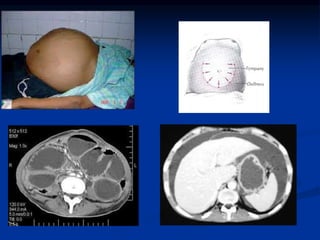

PID / TOA

 History: premenopausal woman, midcycle,

previous STD, vaginal discharge, dysuria, Kehr’s

sign

 Exam: cervical motion tenderness, adnexal

mass

 Pyuria

 US useful to diagnose

PID / TOA History: premenopausal woman, midcycle, previous STD, vaginal discharge, dysuria, Kehr’s sign  Exam: cervical motion tenderness, adnexal mass  Pyuria  US useful to diagnose